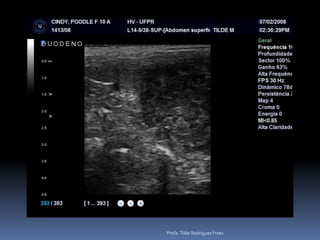

Animal: Cindy, canino, fêmea, 9 anos, Cocker, FC 929/10Suspeita: Pesquisa de metástases – Tumor retal e glândula adeanalProfa. Tilde Rodrigues Froes

Animal: Sacha, canino, fêmea, 11 anosAvaliação – suspeita de HiperadrenocorticismoProfa. Tilde Rodrigues Froes

Animal: Sacha, canino,fêmea, 11 anosAvaliação – suspeita de HiperadrenocorticismoProfa. Tilde Rodrigues Froes